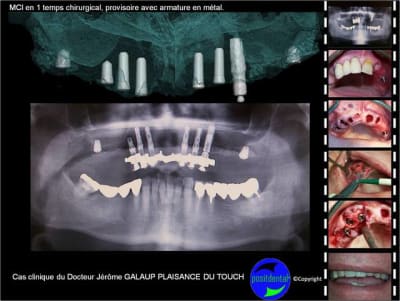

Avulsion, implantation, mise en charge immédiate en 1 temps chirurgical avec provisoire à armature métal.

Le patient a 85 ans (plavix...)

j'aurais posé les implants plus profondement afin d'anticiper l'inevitable resorbtion osseuse post extractionelle

j'essaierais d'avoir les panos pour suivre l'évolution de ce cas.

peut on comparer la résorption osseuse post extractionnelle après une avulsion et avulsion avec MCI?

Pour ma part, dans la mise en charge immédiate je me suis attaché à mettre à disposition un dispositif comprenant des particularités qui me paraissaient indispensables comme par exemple :

- un guide rigide en métal stérilisable pour éviter tout risque de contamination exogène

- des ouvertures pour une irrigation externe efficace

- La réduction du temps entre la pose des implants et leur mise en charge puisque cela se fait dans 1 temps chirurgical

- Une armature rigide dans le bridge provisoire pour correspondre au principe du fixateur externe

Un tel dispositif demande plusieurs jours de préparation pour que l’intervention se déroule rapidement au fauteuil, cela apporte t-il un gain au niveau du capital osseux ? Vos avis m’intéressent

d'apres des cas de mci unitaires que j'ai réalisé ,il me semble que la resorbtion post extractionelle n'est pas negligeable